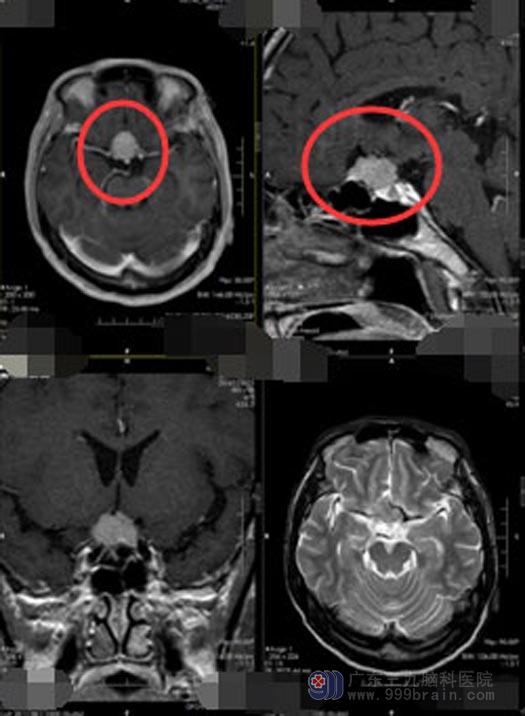

急忙去当地医院,医生告诉他们眼睛是没有问题的,建议脑部影像检查,头颅MR显示:“1,鞍区占位性病变,考虑鞍结节脑膜瘤可能;2,垂体左侧占位,考虑微腺瘤。”一家子人吓坏了,脑袋里面不但有肿瘤,而且还是两个!鉴于当地医院的医疗条件有限,医生建议他们转上级医疗机构。

来到广东三九脑科医院神经外五科后,黄大爷进行了进一步的检查,检查结果提示:1,前颅底占位病变,考虑脑膜瘤;2,垂体后叶Rathke`s囊肿。神经外五科的医生团队经过讨论,一致认为可以采取经鼻蝶手术切除肿瘤,不但手术创伤小、恢复快、而且并发症也少。得到大爷和家属的同意后,2019年10月10日实施了“内镜经鼻蝶鞍结节脑膜瘤+鞍区囊肿切除术”,手术过程很顺利,利用导航精确定位,将两处占位病变全部切除,解除了肿瘤对视神经的压迫。术后病理诊断也于术前诊断一致:1,(鞍结节)脑膜皮细胞型脑膜瘤,WHOI级;2,结合临床及影像,符合(鞍区)Rathke囊肿。

▲手术前